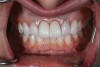

A 29-year-old Caucasian woman presented to the author's (GAM) practice for evaluation of teeth Nos. 8 and 9. The teeth were fractured at the free gingival margin and had sclerosed dental pulps (Figure 7 and Figure 8). The patient's medical history was significant for gastroesophageal reflux disorder (GERD), migraines, narcolepsy, attention deficit hyperactivity disorder (ADHD), and depression. She had no known drug allergies or drug idiosyncrasies and was determined to have an American Society of Anesthesiologists (ASA) II physical status.

At 3 months, osseointegration was confirmed and screw-retained provisionals were used for soft-tissue grooming. Final prosthetic phase completion occurred at 6 months (Figure 12).